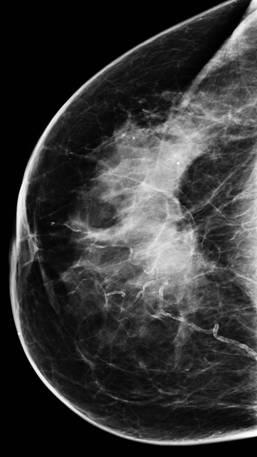

Ung thư vú

» Thông tin: Nữ giới – 76 tuổi.

» Lâm sàng: Khối tuyến vú.